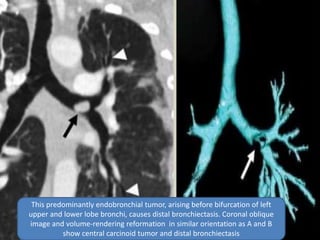

Thisis predominantly endobronchial tumor, arising before bifurcation of

left upper and lower lobe bronchi, causes distal bronchiectasis. Transverse

images of tumor and distal bronchiectasis

 Most carcinoid tumors are primarily

endobronchial lesions, occurring in the central,

main, or segmental bronchi. Some small

tumors are located entirely within the lumen.

However, some display a dominant

extraluminal component with only a small part

of the tumor lying within the airway (iceberg

lesion). A variety of other benign and

malignant neoplasms can also result in

obstruction leading to focal bronchiectasis.

This predominantly endobronchial tumor, arising before bifurcation of left

upper and lower lobe bronchi, causes distal bronchiectasis. Coronal oblique

image and volume-rendering reformation in similar orientation as A and B

show central carcinoid tumor and distal bronchiectasis